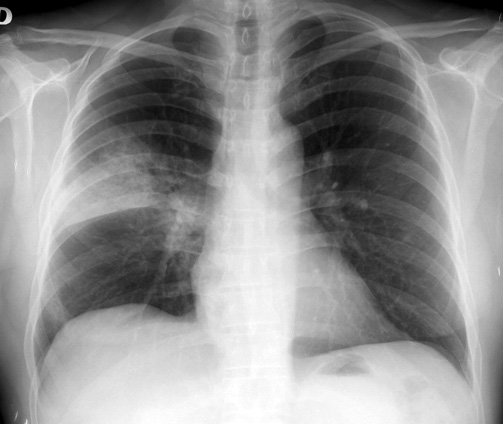

El uso de los inhibidores de la bomba de protones (IBP) se asocia a un aumento de neumonías en pacientes ambulatorios, pero el riesgo podría explicarse por factores de confusión. BMJ, 15 de noviembre de 2016